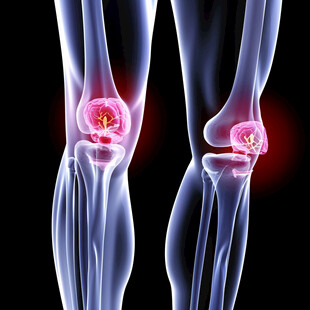

膝关节X光检查 商用作品

膝关节X光检查 商用作品 -

膝关节X光检查 商用作品

膝关节X光检查 商用作品 -

人体膝关节疼痛的医学图解 商用作品

人体膝关节疼痛的医学图解 商用作品 -

人体膝关节3D解剖图 商用作品

人体膝关节3D解剖图 商用作品 -

膝关节X光检查 商用作品

膝关节X光检查 商用作品 -